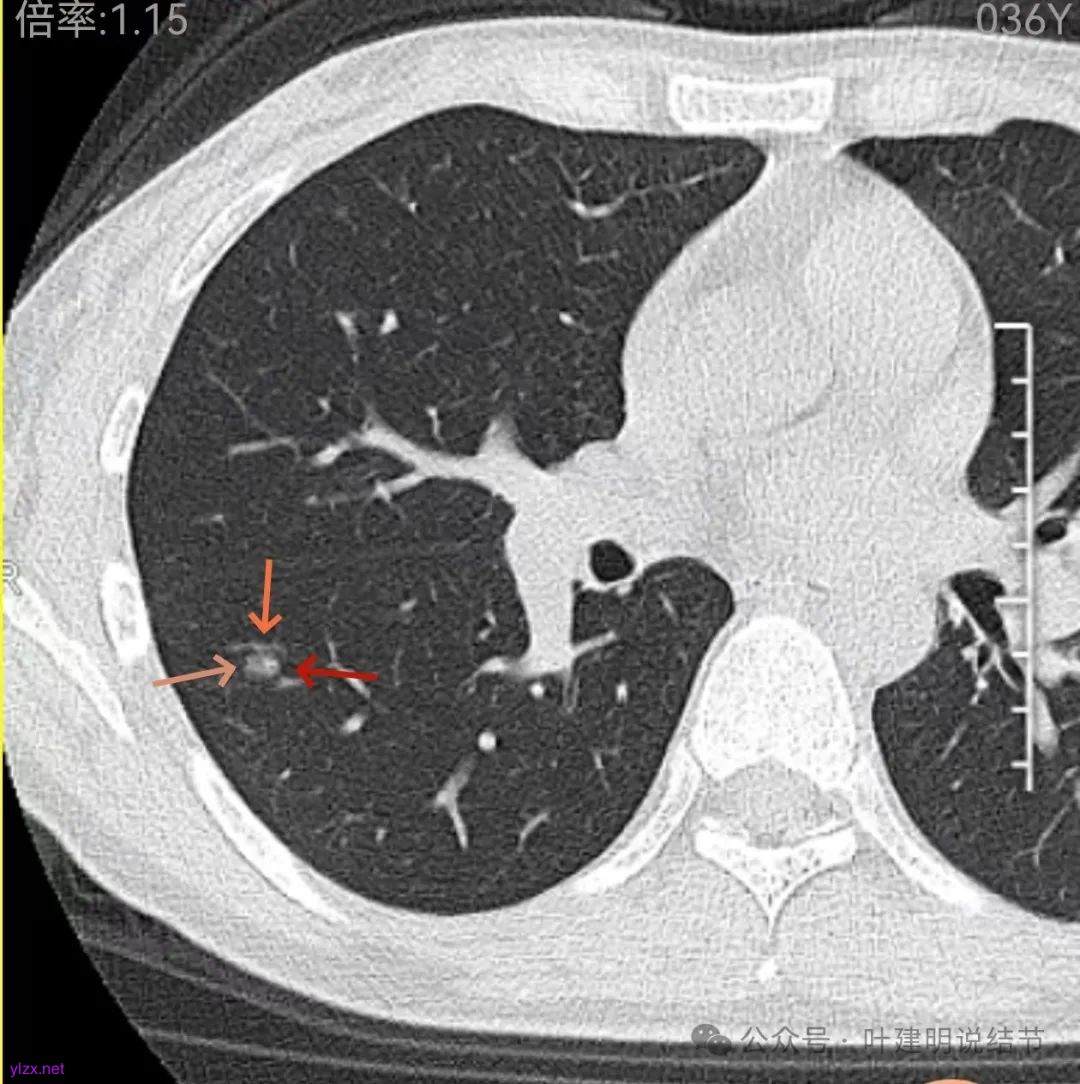

先来看2024年12月的影像:

右下叶磨玻璃结节伴空泡征,轮廓较清,瘤肺边界清楚。

表面不平,轮廓较清,有血管进入,边缘略显毛糙。

病灶内有少许偏实性成分,与血管关系较为密切,局部似有浅分叶的样子。